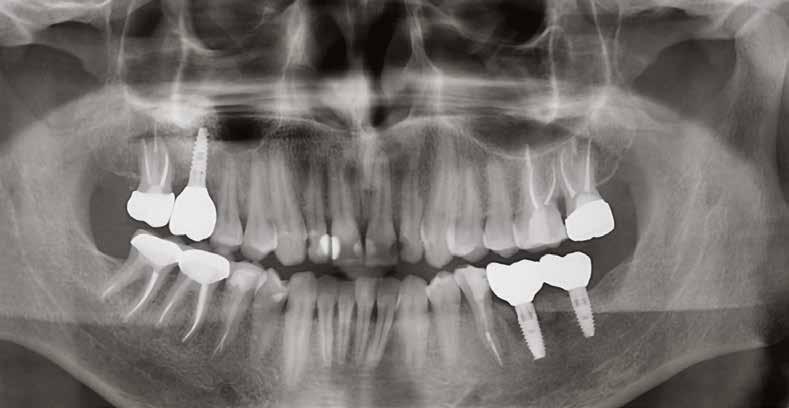

9. ábra: Különböző stádiumnál készített röntgenfelvételek.

10. ábra: Kontroll 18 hónappal később.

lás vált szükségessé, azt sikertelenségnek vettük. Az implantátumok sikerességi aránya 100%-os volt 18 hónap után (9–10. ábra). A előre legyártott azonnali pótlások protetikai sikerességi aránya 90%-os volt. Két esetben a korona levált a felépítményről az első hat hónap során. Egy összefoglaló elemzésben a szerzők összehasonlították a különböző implantátumbehelyezési és terhelési protokollokat (12). A cikkben az azonnali implantáció és azonnali terhelés 98,4%-os

sikerességi aránnyal szerepel. A hagyományos protokollok, ahol a késői implantációt hagyományos késői terhelés követi, a sikerességi arány 97,7%. Meg kell jegyeznünk azonban, hogy a szisztematikus áttekintésbe bevont cikkek között a bizonyítékok szintjében néha lényeges különbségek voltak, amikor az egyes protokollokat összehasonlították. Az azonnali implantáció adatai klinikailag dokumentált adatokra korlátozódtak.